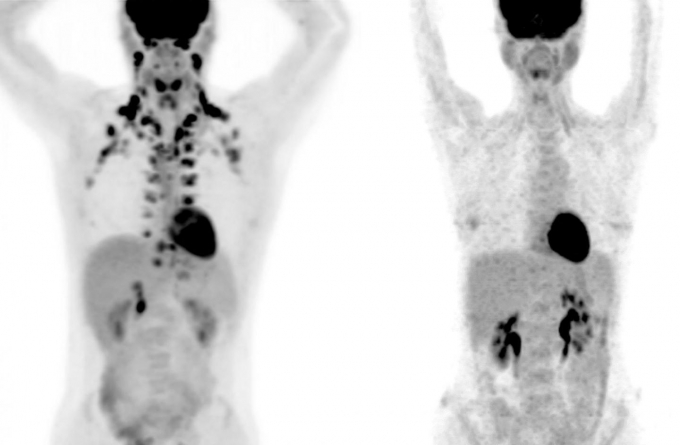

갈색지방은 양전자 단층촬영(PET) 스캔을 해야 어느 부위에 있는지 알아낼 수 있다. PET는 비용이 많이 들고 방사선 노출에 따른 부담도 따른다. 그래서 연구팀은 가까운 거리에 있는 메모리얼 슬론 케터링(MSK) 암 센터의 과학자들과 공동 연구를 했다.

MSK에선 암 진단을 위해 많은 PET 검사가 이뤄지는데, 종양으로 오진하는 걸 막기 위해 PET에 잡힌 갈색지방을 따로 기록한다. 5만2000여 명의 피검자에게서 나온 13만여건의 PET 스캔을 분석한 결과, 거의 10%가 갈색지방을 갖고 있는 것으로 확인됐다.